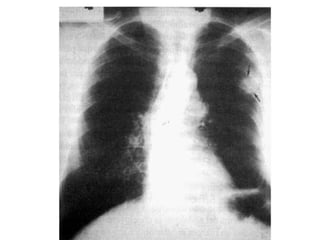

Cáncer de pulmón microcítico (SCLC)

Alrededor del 10% al 15% de todos los cánceres de

pulmón son cáncer de pulmón microcítico (células

pequeñas). A veces se les llama cáncer de células en

avena. Este tipo de cáncer de pulmón suele crecer y

propagarse más rápido que el cáncer de pulmón no

microcítico.